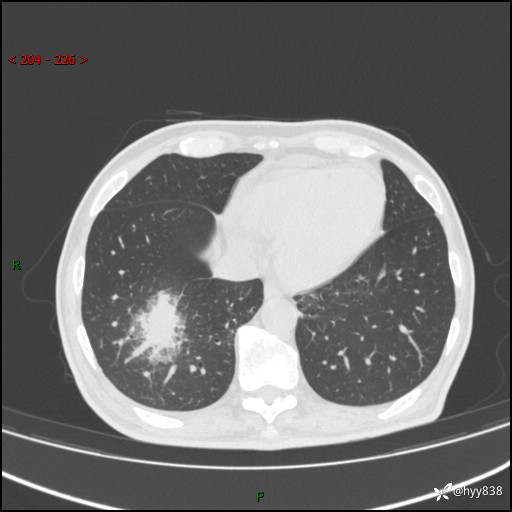

66岁/男,确诊髓系白血病5月,乏力伴气促半月。孤立结节,“晕”的厉害---结果公布~

【患者信息】:66岁/男

【主诉】:确诊髓系白血病5月余,乏力纳差伴气促半月

【现病史及既往史】:患者5月前无明显诱因出现牙龈出血,未重视,2024.5.10社区体检查血常规发现全血细胞减少,后自觉活动后心慌气促,无发热、头痛、咳嗽咳痰、胸痛等,为进一步诊治来我院,门诊以“全血细胞减少”收入,入院后完善相关辅检入院后确诊急性髓系白血病。于2024.06.11给予阿扎胞苷+维奈克拉化疗,给予输血、升白细胞、抗过敏、止血治疗,化疗后粒细胞缺乏,转入层流病房,出现发热,予以抗感染(头孢唑肟、莫西沙星、美罗培南)、抗真菌(卡泊芬净、氟康唑)、利尿、调脂、利胆、护心、护胃、调节免疫(羟氯喹、白芍总苷)、通便、调节胃肠道菌群、营养支持等对症治疗,出院时患者牙龈出血、咳嗽咳痰、腹胀、便秘等不适较前好转,复查血常规提示白细胞计数升高,要求出院,建议继续住院观察,但患者仍要求出院,予以办理。2024-08-06到我院规律化疗,2024-08-08给予阿扎胞苷+维奈克拉化疗,给予输血、升白细胞、抗过敏、止血治疗,化疗后粒细胞缺乏,转入层流病房,出现发热,予以护心、护胃 、营养支持等对症治疗,好转后出院。院外自行停用维纳克拉。半月前患者无明显诱因出现乏力、纳差、活动后气促,无心慌、胸闷,无咳嗽、咳痰,无畏寒、发热等不适,现患者为求进一步诊治来我院,门诊以“急性髓系白血病”收入院。 发病以来,患者精神、饮食欠佳,睡眠一般,大小便如常,体力明显下降,体重无明显减轻。

【检查】:胸部CT平扫